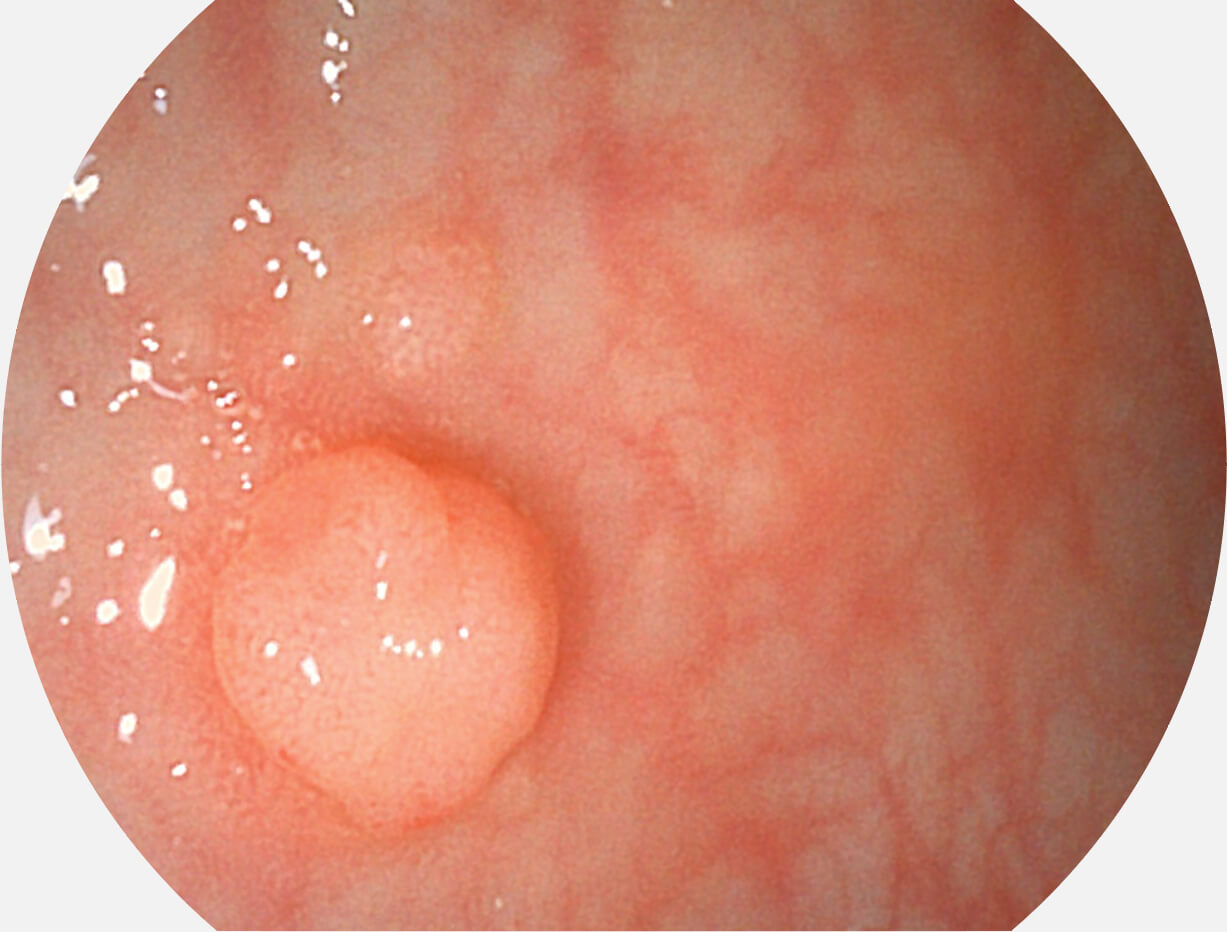

Versatile Intelligent Staining Technology, VIST

强调浅层黏膜结构的同时,保证照明亮度和提升浅层微血管与中层血管颜色对比度,病变边界更清晰。

VIST图像

采用光路合束技术,光谱自由度高,实现了更丰富的照明模式,染色模式SFI及VIST,从远景到近景,助力消化道早期疾病诊断。